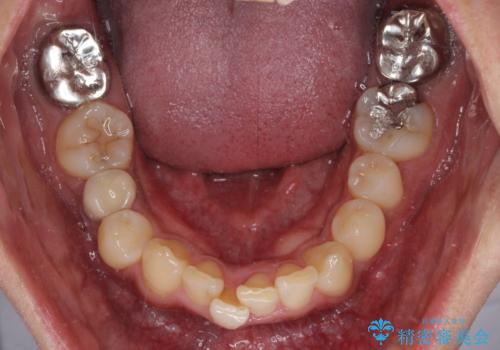

- 上顎の八重歯と正中のズレを気にして来院された患者様です。

八重歯による叢生は著しく、それにより上顎の正中が大きく右にずれている状態でした。

口元の突出感は感じていなかったことと、奥歯の咬み合わせを考慮し、上顎のみ左右の第一小臼歯を抜歯してワイヤー装置にて矯正治療を行うこととしました。